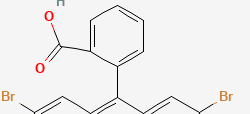

Eosin Y also called C.I. 45380 or C.I. Acid Red 87, is the form of eosin most commonly used in histology, most notably in the H&E stain. Eosin Y is also widely used in the Papanicolaou stain and the Romanowsky type cytologic stains.

Chemical formula: C20H6Br4Na2O5